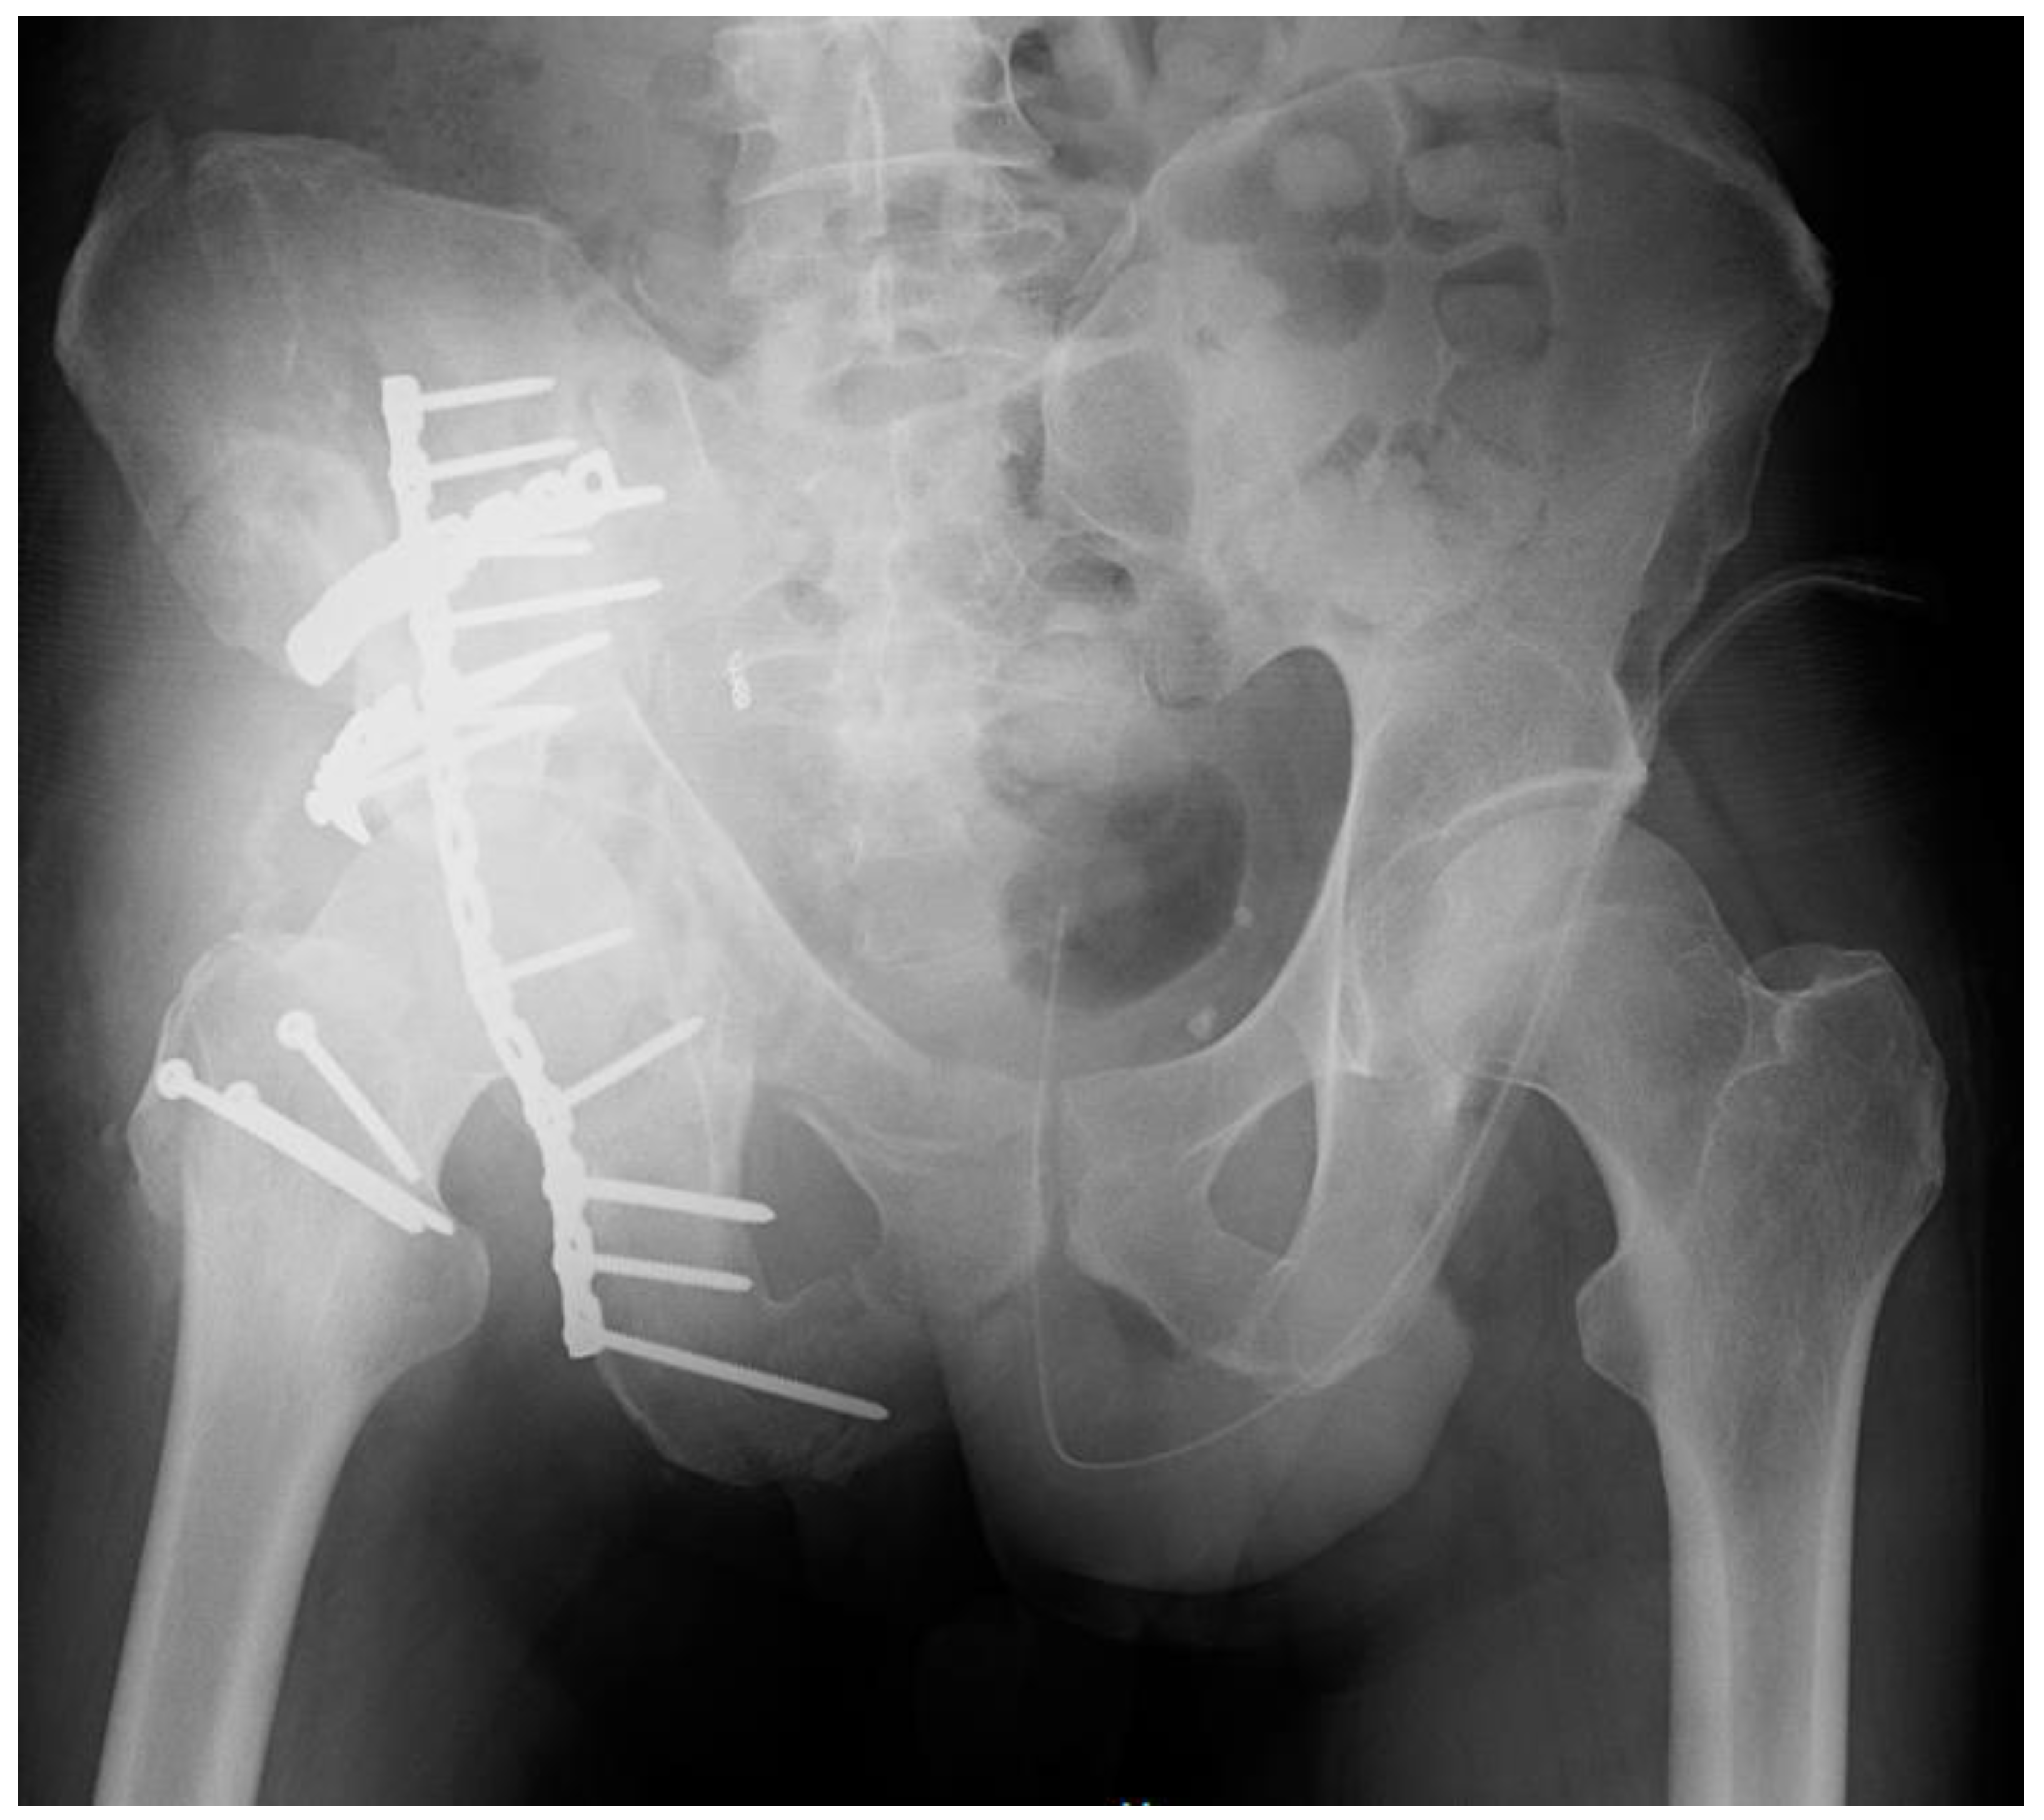

2. Case Report